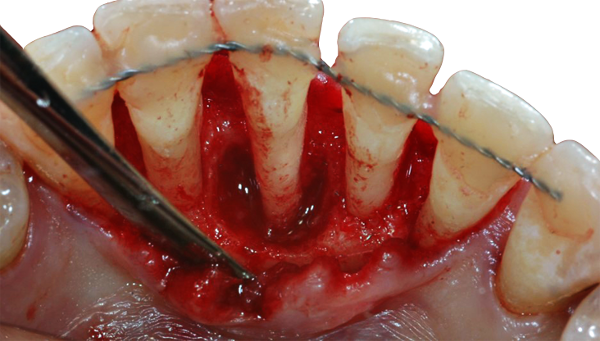

Os procedimentos cirúrgicos têm como principais objetivos facilitar o acesso para um alisamento radicular adequado, o estabelecimento de um contorno gengival favorável e uma melhoria da arquitetura dentogengival de forma a facilitar os procedimentos de controlo de placa bacteriana pelo paciente e pelo médico dentista, permitindo desta forma uma adequada manutenção da saúde periodontal, com redução da incidência de recidivas ao longo do tratamento periodontal de suporte.

Ao longo dos anos foram desenvolvidas diferentes técnicas cirúrgicas para tratamento da periodontite, destacando-se técnicas ressetivas e técnicas regenerativas.

Nesta apresentação serão referidas as distintas técnicas realizadas no contexto do tratamento periodontal cirúrgico. Os resultados comparativos dos diferentes tipos de procedimentos serão discutidos, ilustrando com casos clínicos.